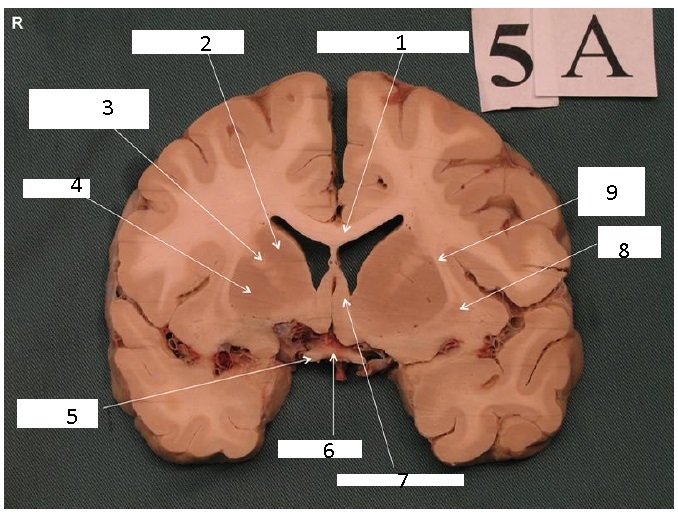

Identify 1

Body of Corpus Callosum

Identify 2

Caudate Nucleus

Identify 3

Anterior Limb of Internal Capsule

Identify 4

Putamen

Identify 5 and 6

5: Optic N

6: Optic Chiasm